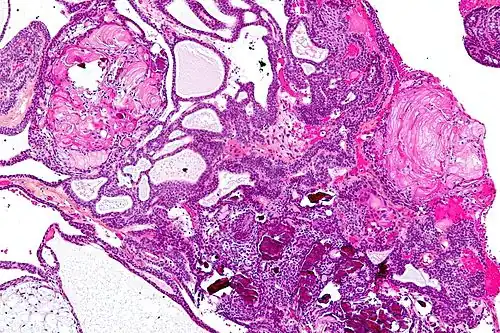

| Very low magnification micrograph of an adamantinomatous craniopharyngioma. HPS stain. | |

On macroscopic examination, craniopharyngiomas are cystic or partially cystic with solid areas. On light microscopy, the cysts are seen to be lined by stratified squamous epithelium. Keratin pearls may also be seen. The cysts are usually filled with a yellow, viscous fluid rich in cholesterol crystals. Of a long list of possible symptoms, the most common presentations include headaches, growth failure, and bitemporal hemianopsia.

Micrograph showing the characteristic features of an adamantinomatous craniopharyngioma - cystic spaces, calcifications, and "wet" keratin, HPS stain -